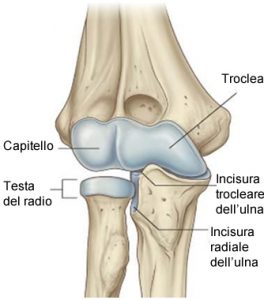

L’articolazione del gomito è composta dalla parte inferiore dell’omero nelle sue due parti (troclea e condilo) e le estremità superiori delle ossa dell’avambraccio che sono il Radio e l’Ulna (con il capitello radiale e la cavità sigmoidea dell’ulna). Attraverso queste superfici è possibile il movimento di flesso estensione del gomito e di rotazione dell’avambraccio (prono-supinazione).

Grazie proprio al capitello radiale, ai legamenti tra radio e ulna e alle estremità inferiori di queste due ossa è possibile inoltre eseguire il movimento di prono-supinazione, cioè la rotazione dell’avambraccio in un senso o nell’altro.